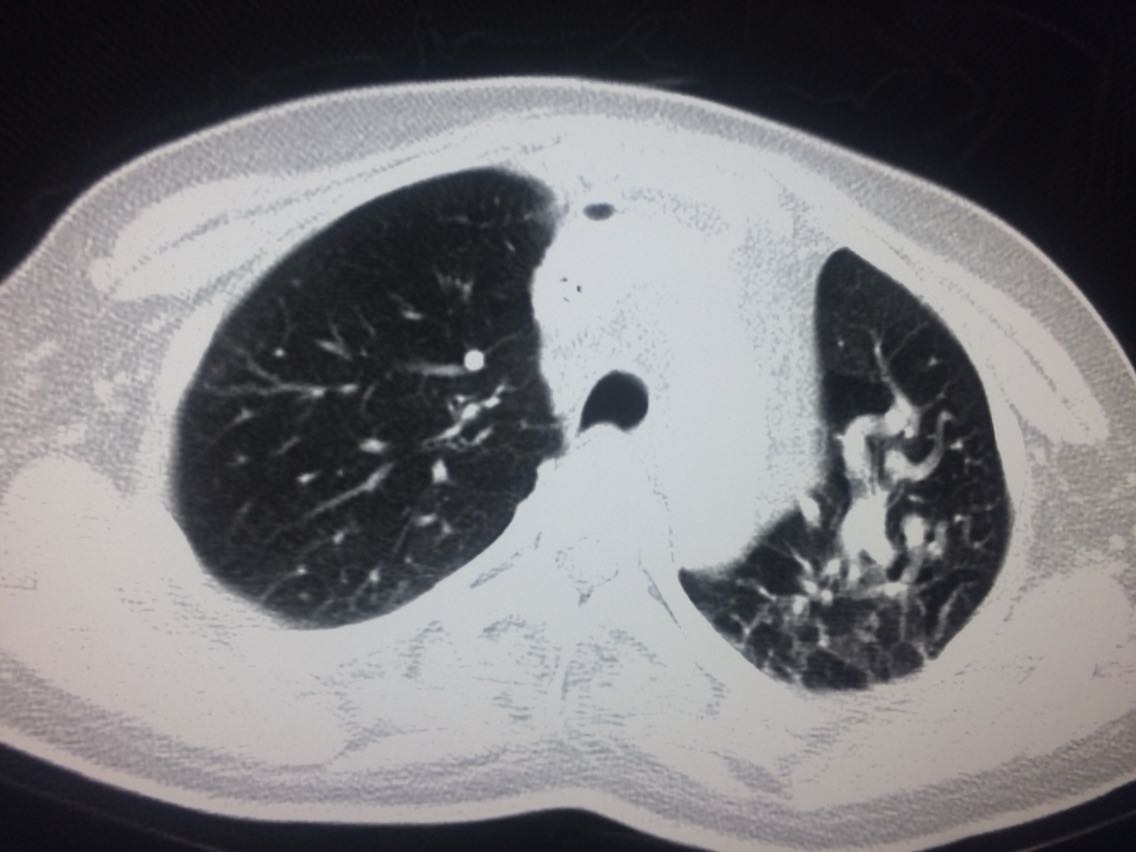

诊断,肺动脉高压。 鉴别诊断,肺动脉栓塞。 影像诊断,肺动脉高压,肺门区出现残根征,肺动脉扩张,肺动脉段膨隆,心影增大。CTA见迂曲增宽的肺动脉。 肺栓塞,影像可见典型充型缺损影,伴随肺纹理的减少。 治疗以对症处理为主,病人病史14年。 讨论诊断和鉴别诊断? 随访,症状好转。